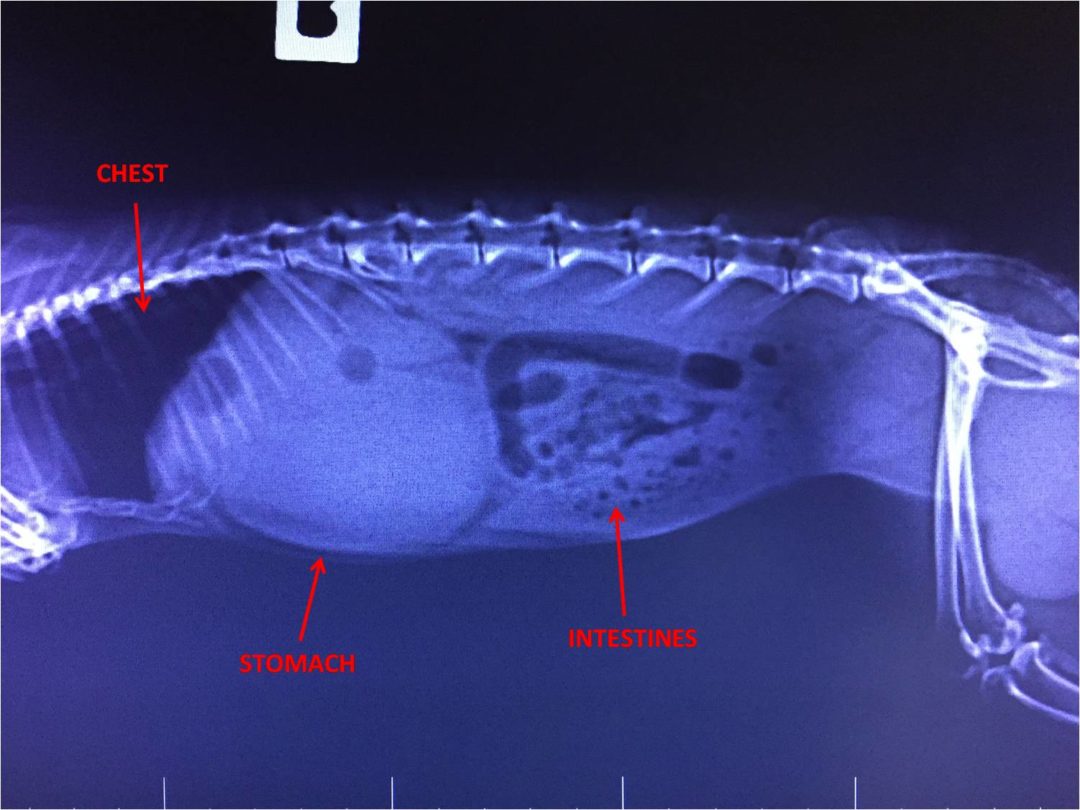

Gastrointestinal stasis in Rabbits — Westley’s World